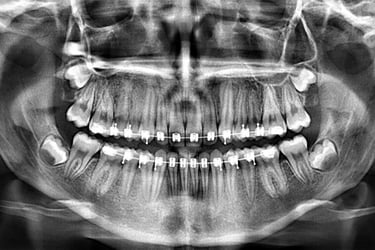

PANORÁMICA DIGITAL